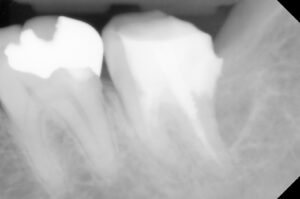

冠を被せた第二大臼歯の問題以上に、痛みは

第一大臼歯の詰め物の下が虫歯になっている

ことを説明し、処置内容と概算費用をつたえ

レントゲンでは神経の詰め物の状態の違い→

歯根の崩壊度は経時的なもの?→